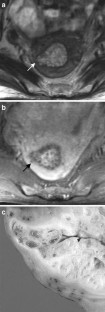

The endometrial cavity may demonstrate various imaging manifestations such as normal, reactive, inflammatory, and benign and malignant neoplasms. We evaluated usual and unusual magnetic resonance imaging (MRI) findings of the uterine endometrial cavity, and described the diagnostic clues to differential diagnoses. Surgically proven pathologies of the uterine endometrial cavity were evaluated retrospectively with pathologic correlation. The pathologies included benign endometrial neoplasms such as endometrial hyperplasia and polyp, malignant endometrial neoplasms such as endometrial carcinoma and carcinosarcoma, endometrial–myometrial neoplasm such as endometrial stromal sarcoma, pregnancy-related lesions in the endometrial cavity such as gestational trophoblastic diseases (hydatidiform mole, invasive mole and choriocarcinoma) and placental polyp, myometrial lesions simulating endometrial lesions such as submucosal leiomyoma and some adenomyosis, endometrial neoplasms simulating myometrial lesions such as adenomyomatous polyp and endometrial lesions arising in the hemicavity of a septate/bicornate uterus, and fluid collections in the uterine cavity (hydro/hemato/pyometra). It is important to recognize various imaging findings in these diseases, in order to make a correct preoperative diagnosis.

Fig. 2